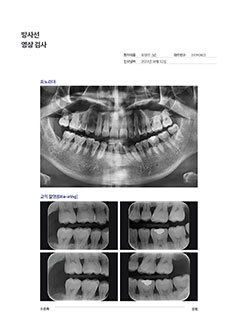

[ 파노라마 ]

파노라마는 전반적인 치아의 상태와 배열, 교합관계, 턱뼈 상태를 보여줍니다.

잇몸뼈가 흡수된 부위가 있는지, 치아 뿌리 끝에 염증은 없는지, 기존 보철물의 상태가 어떤지, 치아결손 부위가 있는지 등을 파악할 수 있습니다.

Oral Photography / Bite-Wing Radiography / Periapical Radiograph

[ 교익 촬영 ]

상, 하악 치아의 머리 부분만을 보기 위한 방사선 촬영 기법으로 조기 발견이 어려운 치아 인접

[ 치근단 촬영 ]

* 필요한 경우 진행문제 있는 치아를 더욱 정밀하게 확대해서 보기 위한 방사선 촬영 기법으로 치아 뿌리 끝 염증, 신경 치료 상태, 일반 충치 및 2차 충치 등을 관찰할 수 있습니다.